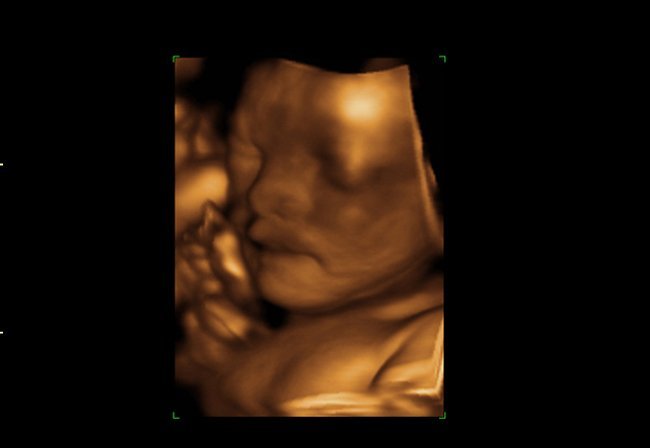

El estudio, que analiza las secuencias de vídeo 4D de 15 fetos sanos (ocho femeninos y siete masculinos) de entre 24 a 36 semanas de gestación, distingue claramente el bostezo, del no bostezo o la boca abierta, centrándose an la duración de la apertura de la boca.